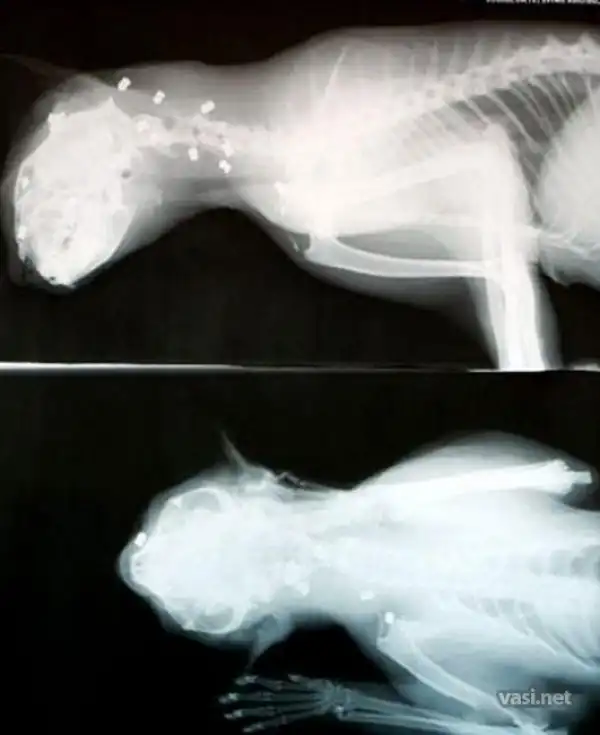

Подонки всадили ему в голову 27 пуль, но он ВЫЖИЛ!

15 пуль извлек ветеринар, 5 - хозяйка кота, а остальные так и не нашли

Язык, нос и шея кота продырявлены, но после предстоящей операции он будет жить.